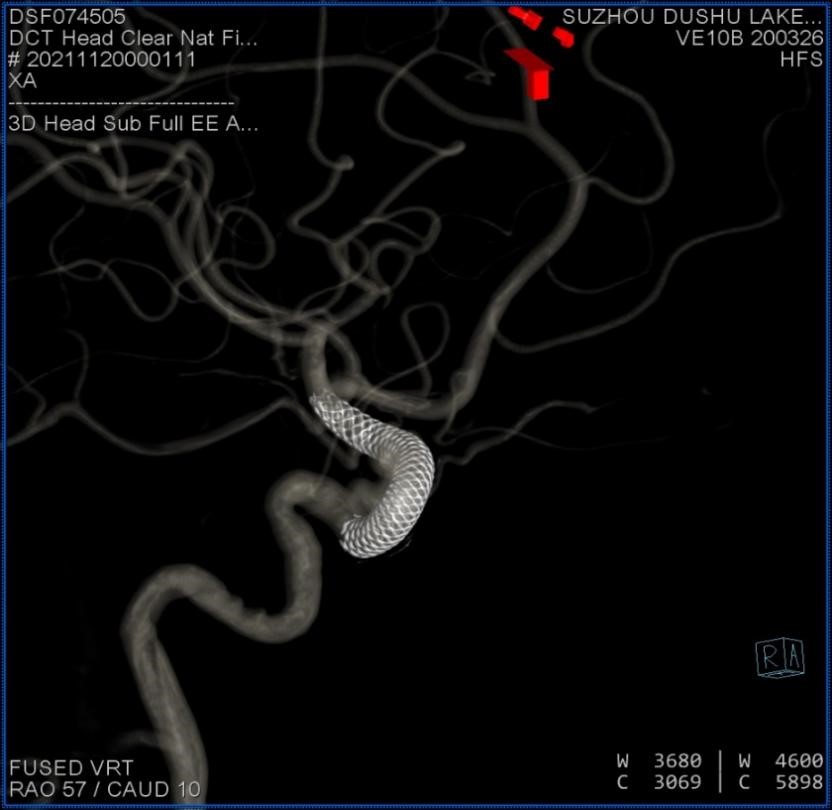

支架导管到位后,缓慢释放血流导向密网支架。

释放完全,即刻可见造影剂在动脉瘤腔内滞留

术中Dyna CT提示支架释放良好

术中影像融合提示支架贴壁良好

眼动脉,脉络膜前动脉,后交通动脉血流无影响

血流导向密网支架重建